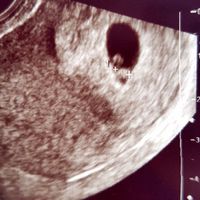

Ecografia

Angela in Future mamme, Il 11 Aprile 2018 alle 17:55

Ciao mammine, mi rivolgo alle esperte di ecografie. Dalle misure della prima eco mi dava che ero a 5+5, invece contando dall'ultima mestruazione ero a 7+2. Lunedì ho la prossima ecografia e contando...

Lorila, giovedì 12-Apr-18 8 436